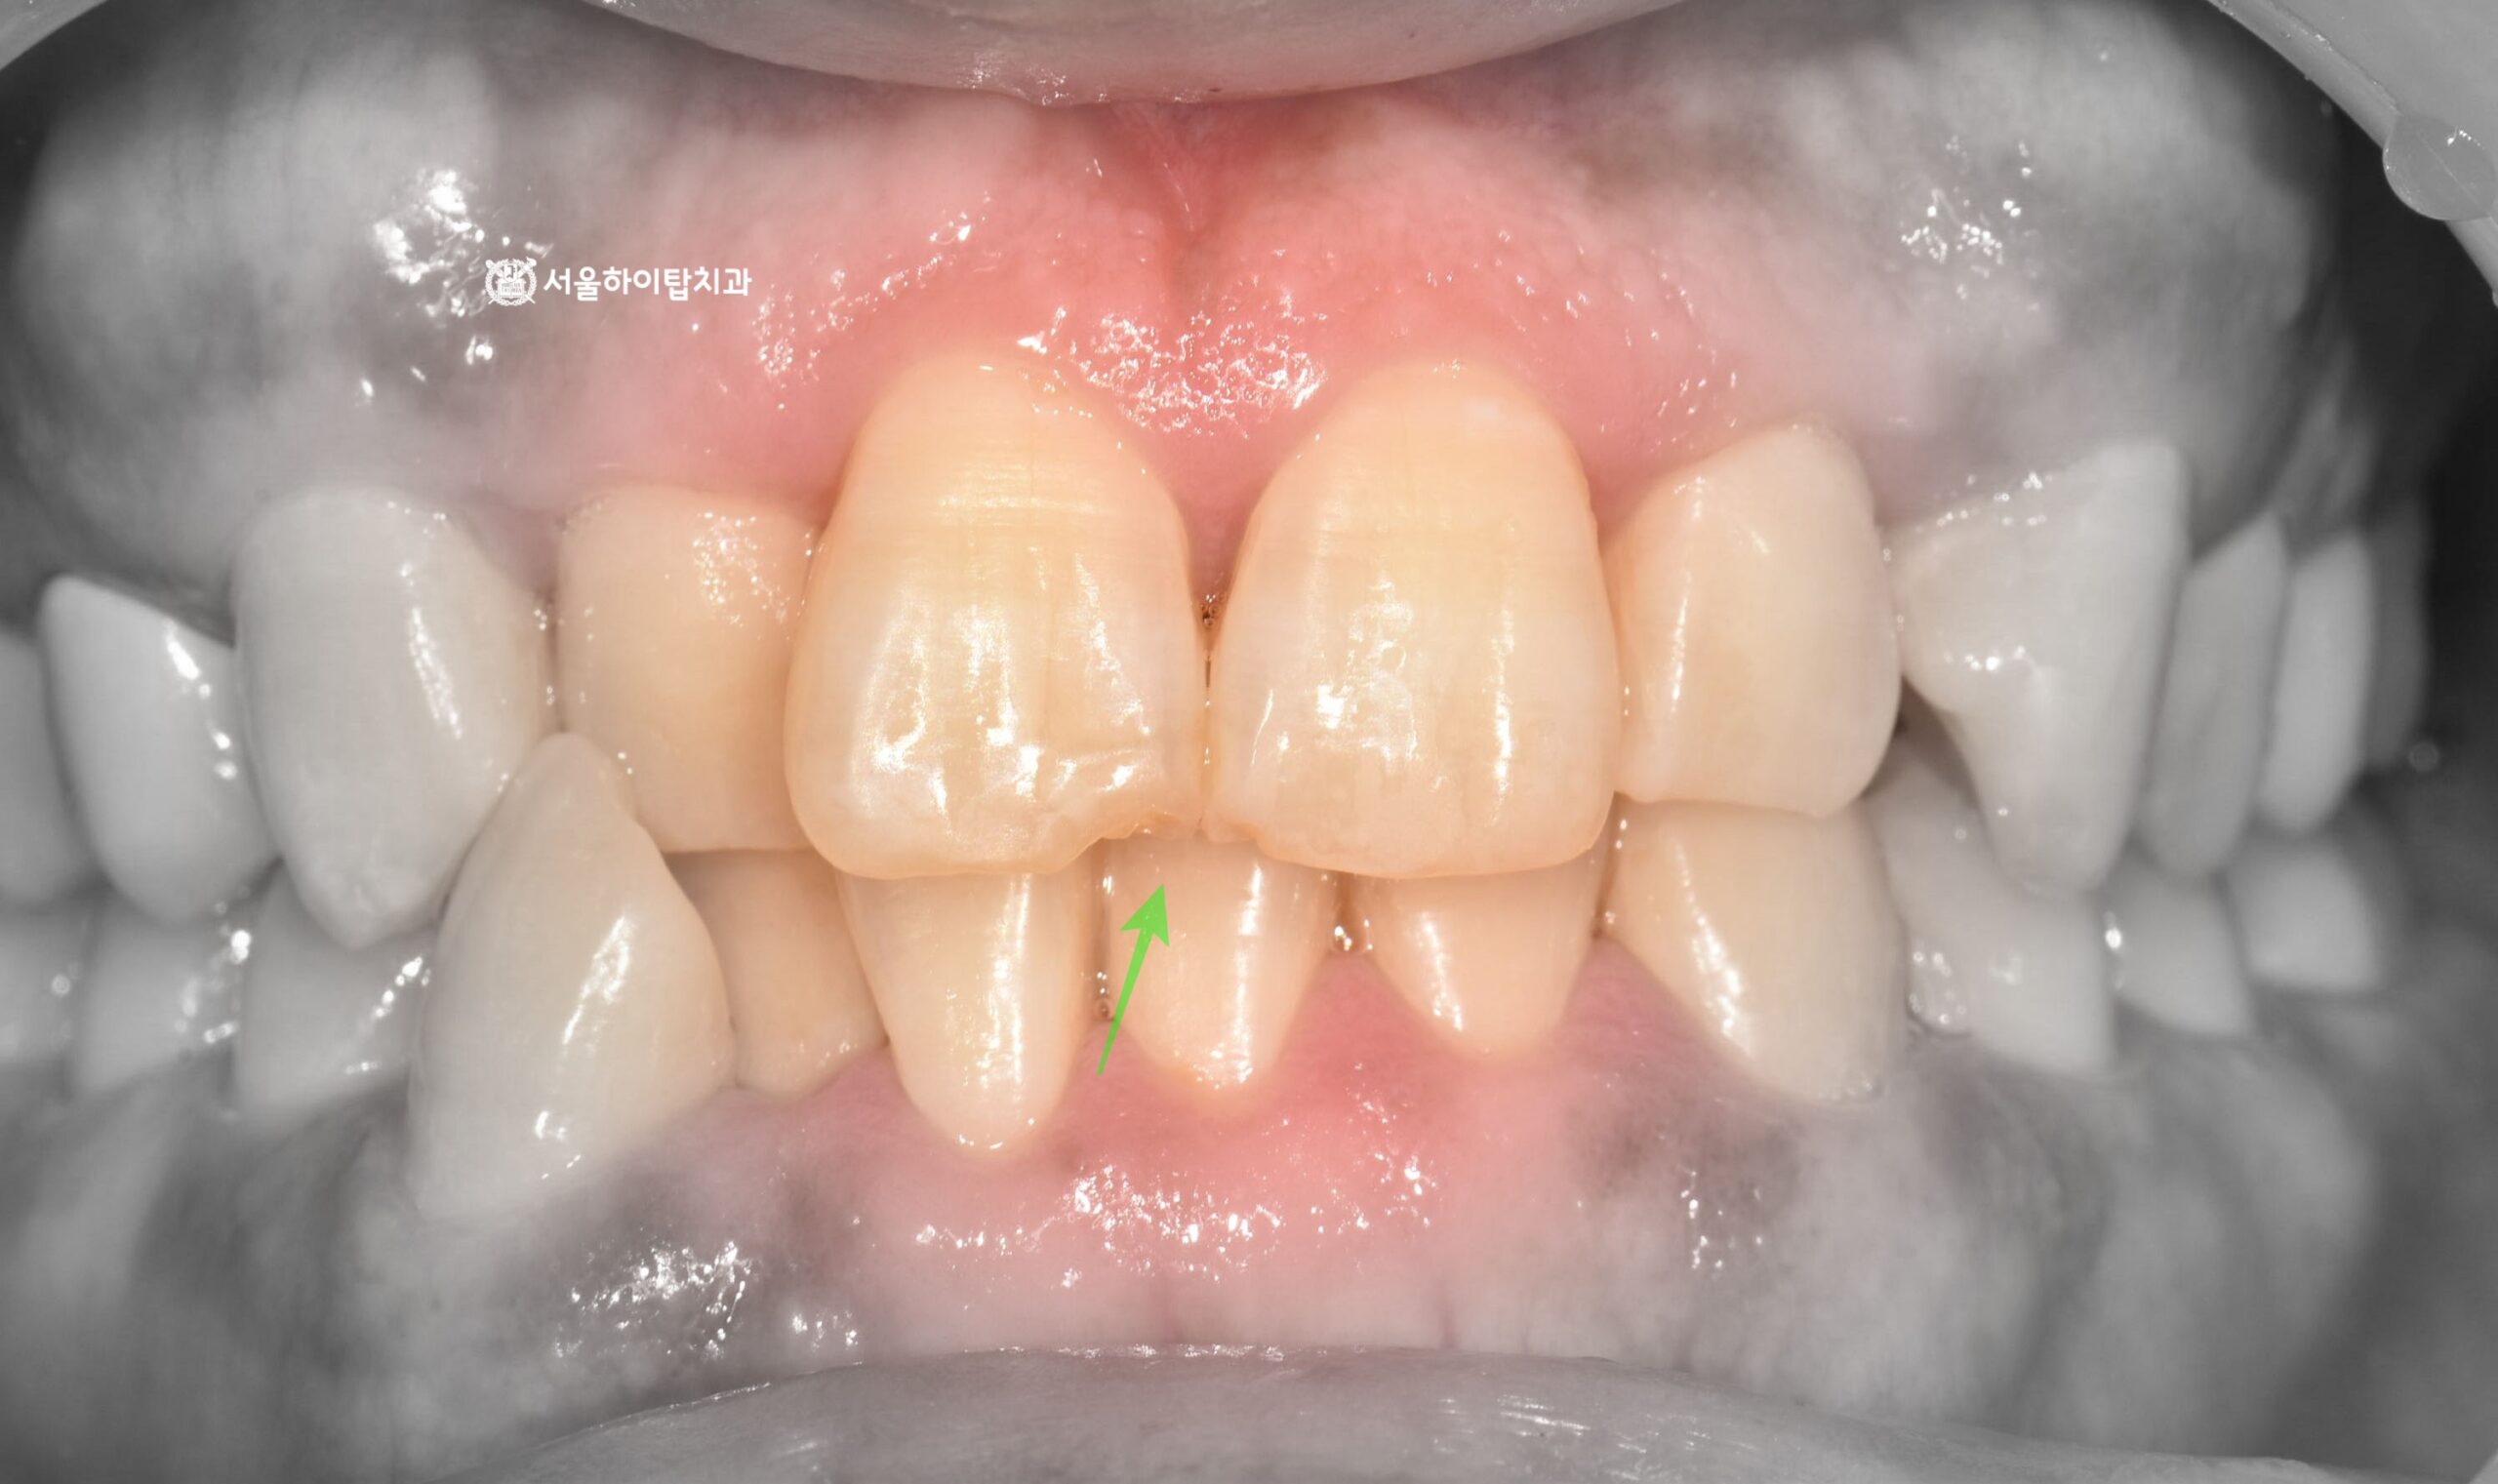

십정동 치과 어금니 상실 후 CT 기반 정밀 진단 후 진행한 당일 즉시 임플란트 진행 과정 동암역 치과, 불편한 앞니 바로 신경치료할까요? 검사부터 치료까지 (치근단 염증 · PFM 크라운) 주안역 치과 치아 흔들림(동요도 3도) 발치 후 임플란트 진행 과정 부평 치과 치아 머리·목 부분에 진행된 충치, 신경치료 과정 및 장기적 파절 가능성 안내 십정동 치과 앞니에서 파절이 쉽게 일어나는 부위가 있다? 절단연 파절 후 레진 수복 과정 간석오거리역 치과 치수까지 침범한 충치, 발치 후 임플란트 진행 과정 (정기검진과 조기 치료의 중요성) 만수동 치과 80대 고령환자, 심한 충치 치아 발치 후 임플란트 수술 과정 (발치가 필요한 충치?) 백운역 치과 신경치료 후 앞니 치아가 파절되기 쉬운 이유가 무엇일까? 임플란트 수술 과정 주안동 치과 70대 고령 환자│뿌리까지 이어진 치아 파절의 원인과 임플란트 수술 과정 간석동 치과│치주염으로 인한 골 흡수와 치아 흔들림, 뼈 이식을 동반한 임플란트 치료 과정 부평 치과 심한 치아 통증 엑스레이에서 보이지 않는 치수염? 신경치료와 크라운 수복 과정 만수동 치과|성장기 치아 상실, 왜 성인이 되어 임플란트를 했을까요? (상악동 거상술 동반) 십정동 치과 상실된 치아가 불러오는 연쇄적 문제? 치조골 흡수와 기울어진 어금니, 뼈이식 동반 임플란트 과정 동암역 치과 : 균형 잡힌 저작이 중요한 이유, 전반적으로 손상된 치아 및 잇몸 임플란트를 통해 저작 기능 개선 간석역 치과 치주염으로 인한 치조골 흡수, 치아 파절 및 마모까지 임플란트 가상 시뮬레이션을 통한 안전한 수술 과정 1 2 Next Archives 2026년 4월 2026년 3월 2026년 2월 2026년 1월 2025년 12월 2025년 11월 Categories 미분류 신경치료 심미 치료 임플란트 BACK TO TOP